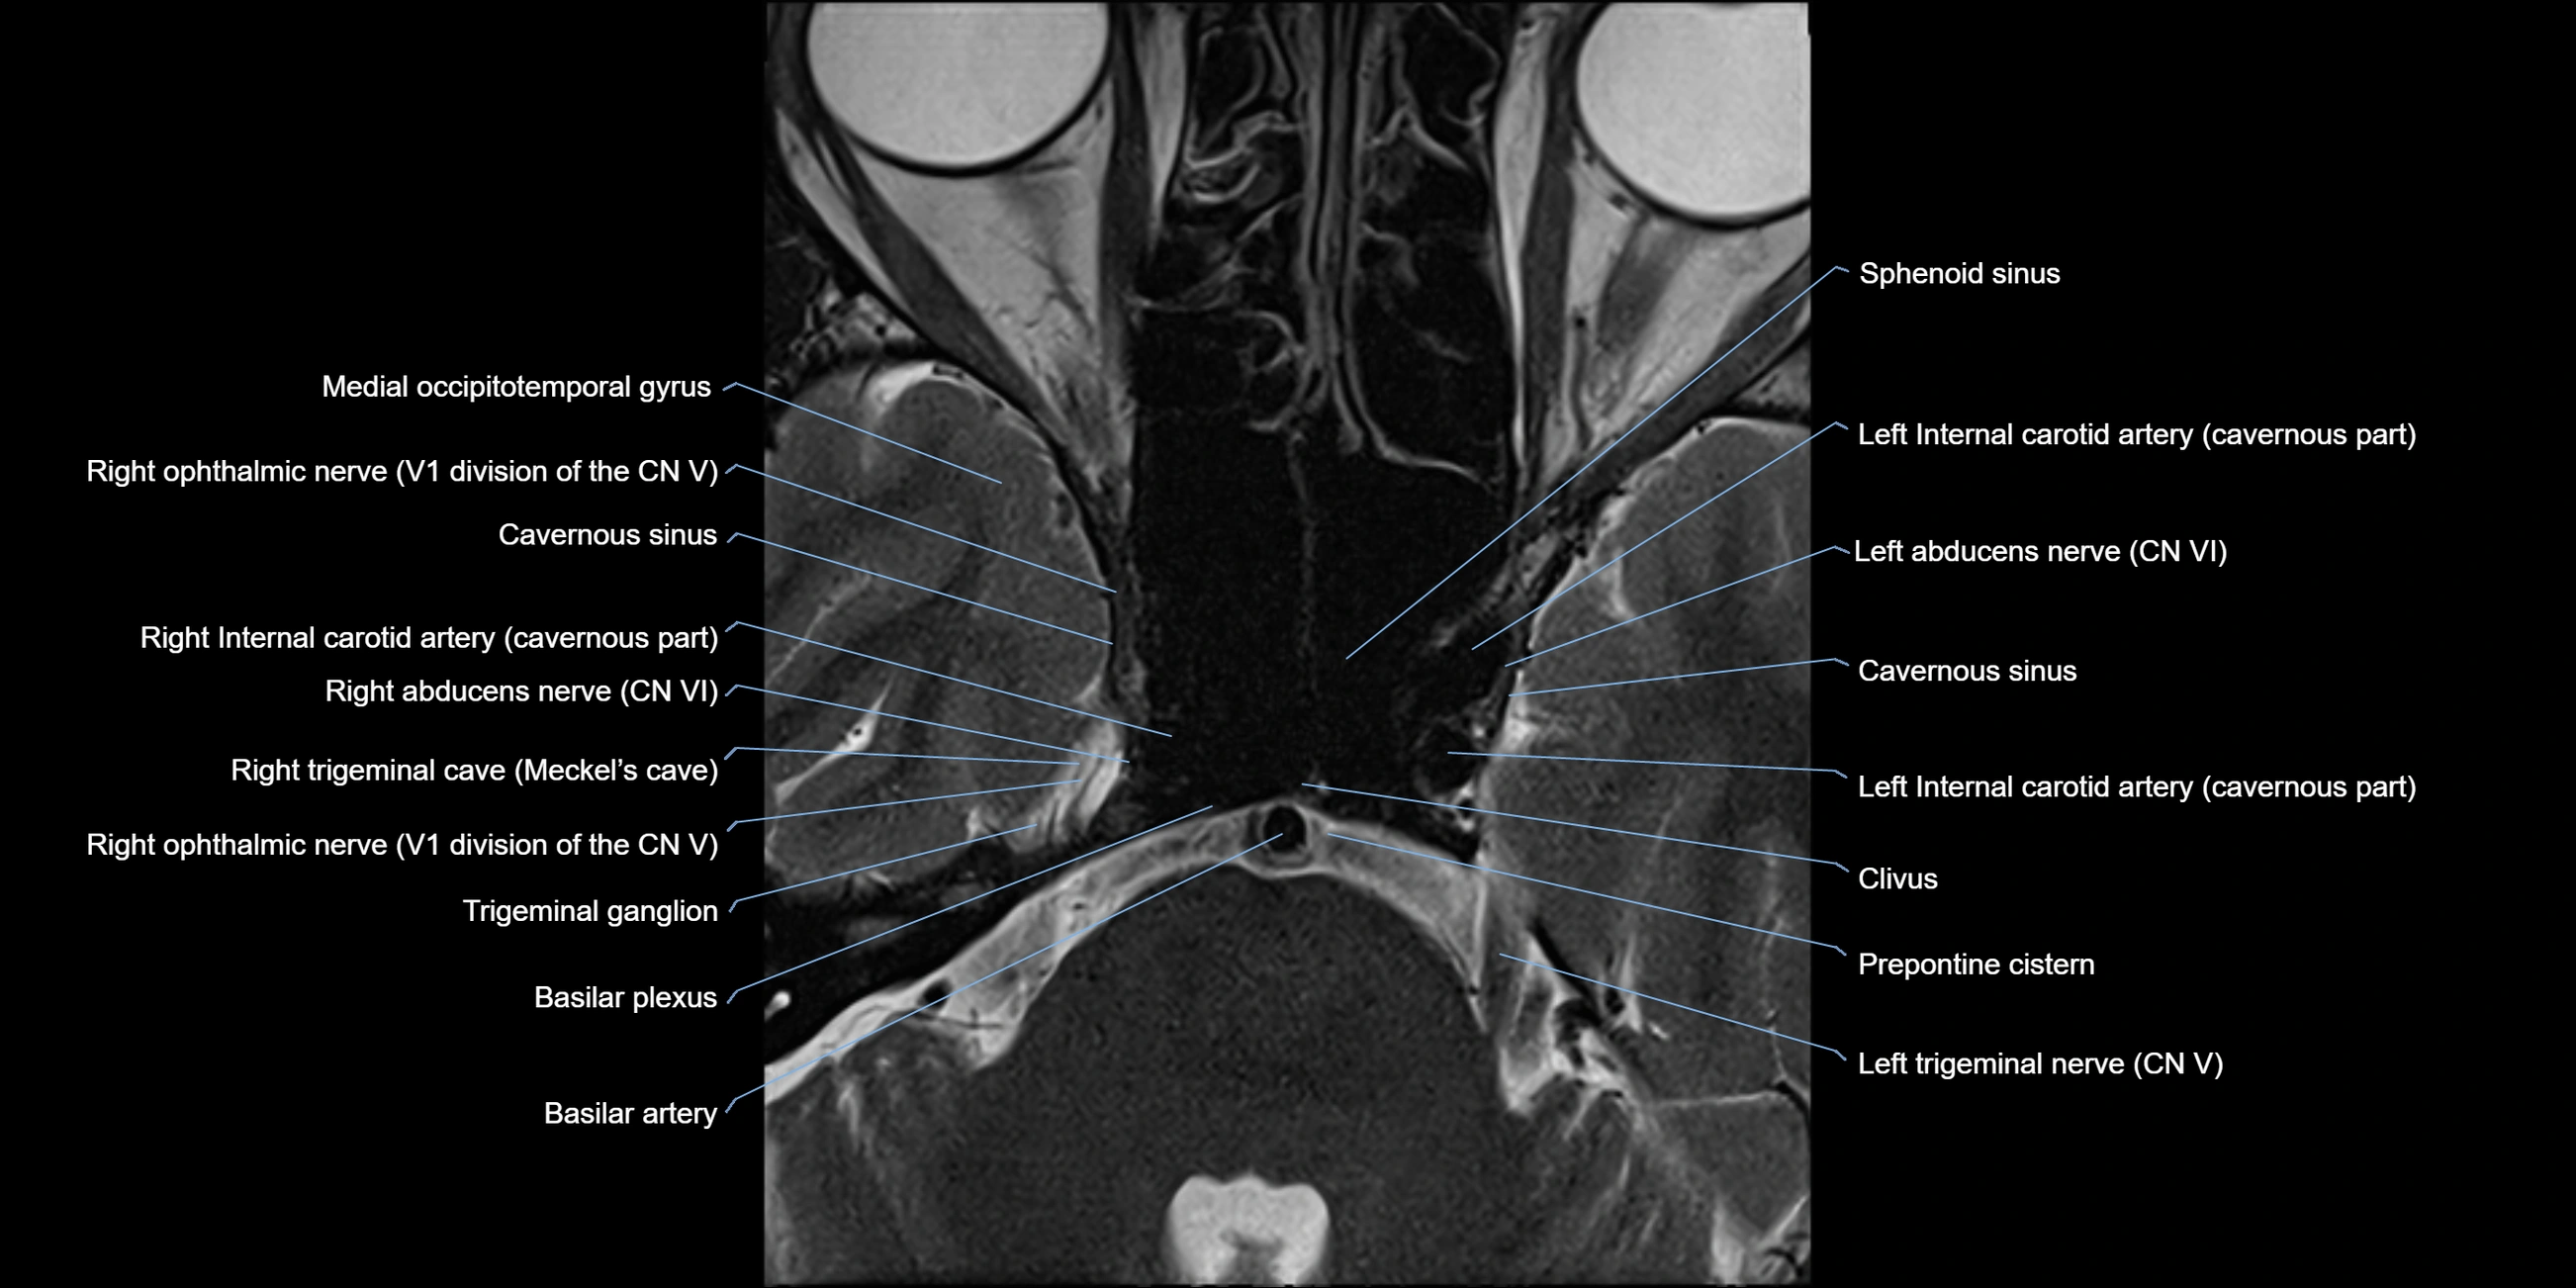

MRI Appearance

The abducens nerve is a small, thin, linear structure

Best visualized on high-resolution T2-weighted 3D MRI sequences (e.g., FIESTA or CISS)

Seen as a hypointense (dark) line running from the brainstem at the pontomedullary junction, traversing the prepontine cistern, and entering Dorello’s canal under the petrosphenoidal ligament, then into the cavernous sinus, and finally the orbit

May be challenging to visualize in standard MRI due to its small size

Pathology may be inferred by absence, displacement, or enhancement of the nerve